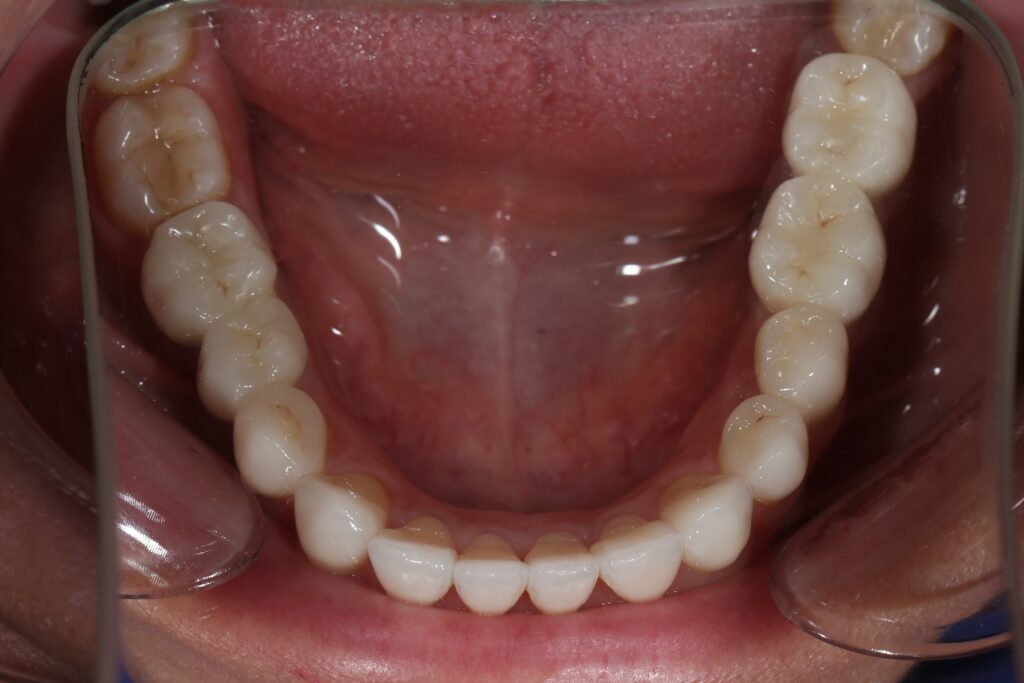

Этап имплантации и протезирования и результаты

Затем были установлены имплантаты Megagen AnyOne.

Спустя 3 месяца после установки имплантатов была произведена замена несостоятельных реставраций и пломб для избежания развития вторичного кариеса под винирами и коронками.

Сделано препарирование зубов на верхней и нижней челюстях с контролем глубины (0.7-0.8 мм) под керамические реставрации. Сняты оттиски с имплантатов.

Установлены временные виниры и коронки из пластика. Спустя 26 дней были зафиксированы керамические виниры и коронки на своих зубах и циркониевые коронки на имплантатах.

Результаты